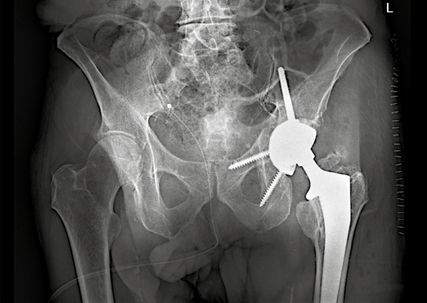

Hochbetagte Patientinnen und Patienten können in der Regel nicht mobilisiert werden, ohne die betroffene Extremität voll zu belasten. Die Ursachen hierfür können dabei sowohl körperlicher als auch kognitiver Natur sein. In diesen Fällen gewinnt die primäre endoprothetische Versorgung mit Rekonstruktionspfanne an Bedeutung (Replace-in-situ-Prinzip). Diese gewährleistet in Kombination mit der zentralen Ileumschraube eine sofortige stabile Primärverankerung der Hüftpfanne auch bei komplexen Frakturmustern und ermöglicht somit eine frühe Vollbelastung sowie Remobilisation. Ein Beispiel einer solchen Rekonstruktionspfanne stellt die Mutars® PRS (Pelvic Revision Shell) dar. Die zementfrei implantierte Rekonstruktionsschale von Implantcast zeigt Abbildung 1.